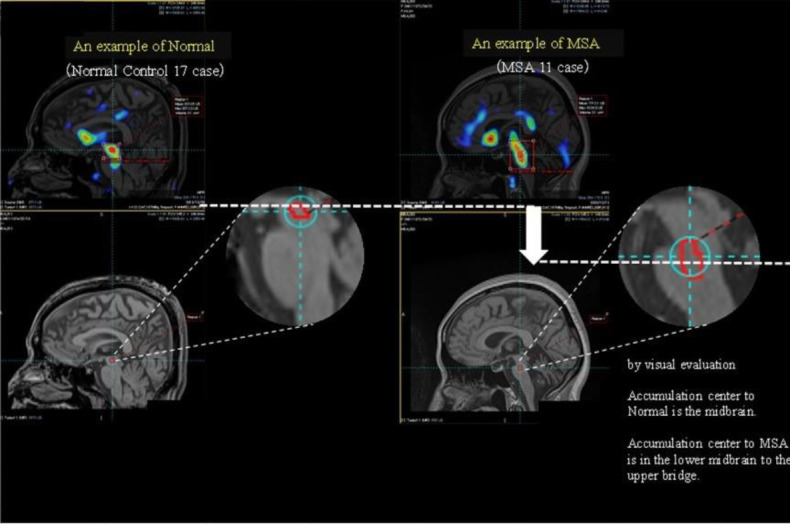

Results: The SERT accumulation site was visualised as an SBR value on MR images. The accumulation distribution (SERT distribution) on the SBR images significantly differed between the healthy subjects and patients with MSA.

Conclusion: SERT accumulation was noted in the brain-stem region, indicating that SBR imaging was useful for viewing and quantifying SERT accumulation.